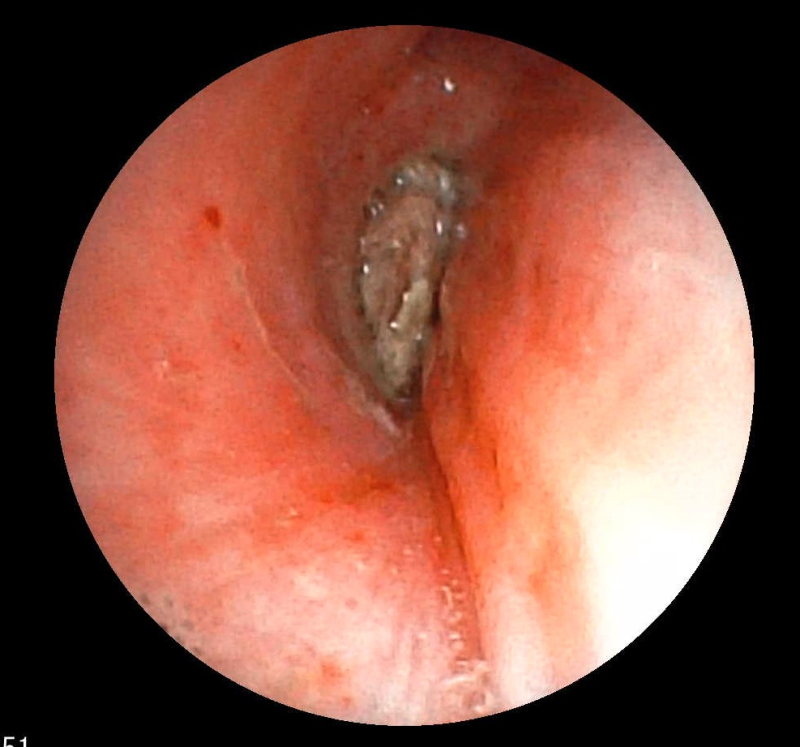

Hình ảnh dị vật góc cạnh khoảng 1cm là hạt kha tử hình bầu dục, bề mặt trơn nhẵn, hai đầu nhọn nằm chắn, gây bít tắc trong lòng phế quản gốc phải trên màn hình nội soi phế quản

Ekip của bác sĩ CKI Phạm Thị Út Trang – Phó Trưởng Khoa Nội hô hấp đã phối hợp với bác sĩ gây mê hồi sức đã nhanh chóng tiến hành nội soi phế quản ống mềm, phát hiện dị vật góc cạnh khoảng 1cm là hạt kha tử hình bầu dục, bề mặt trơn nhẵn, hai đầu nhọn nằm chắn, gây bít tắc trong lòng phế quản gốc phải, ngay sát vị trí chia nhánh phế quản phân thùy- khu vực giải phẫu hẹp, góc rẽ nhánh phức tạp khiến việc gắp dị vật gặp khó khăn. Ekip nội soi can thiệp đã khéo léo tiếp cận và thành công gắp dị vật ra khỏi lòng phế quản. Sau can thiệp, sức khỏe của bệnh nhân ổn định, thở dễ dàng, không còn cảm giác tức ngực, được xuất viện sau 24h theo dõi.